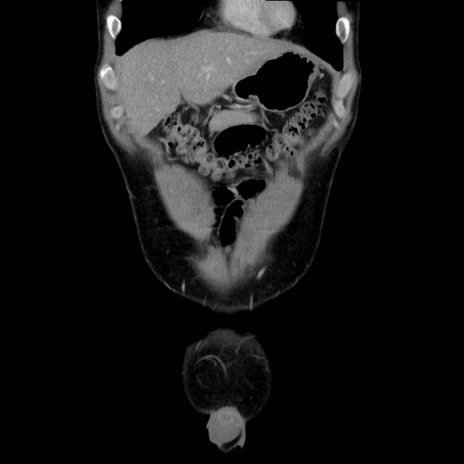

症例36(冠状断像)

【症例】20歳代 男性

【主訴】心窩部痛

【現病歴】今朝より上腹部痛あり。一旦軽快していたが再度出現したため救急要請。昨日夕に白身の魚を含む刺身を食べた。

【身体所見】BP 136/89mmHg、HR 74/min、BT 37.0℃、腹部:膨満、軟、心窩部に圧痛あり。反跳痛なし、筋性防御なし、腸雑音やや亢進あり。

【データ】WBC 17700、CRP 0.48

横断像